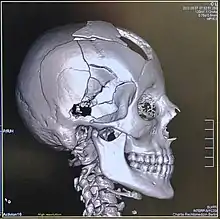

Volume rendering

A threshold value of radiodensity is set by the operator (e.g., a level that corresponds to bone). With the help of edge detection image processing algorithms a 3D model can be constructed from the initial data and displayed on screen. Various thresholds can be used to get multiple models, each anatomical component such as muscle, bone and cartilage can be differentiated on the basis of different colours given to them. However, this mode of operation cannot show interior structures.[113]

Surface rendering is limited technique as it displays only the surfaces that meet a particular threshold density, and which are towards the viewer. However, In volume rendering, transparency, colours and shading are used which makes it easy to present a volume in a single image. For example, Pelvic bones could be displayed as semi-transparent, so that, even viewing at an oblique angle one part of the image does not hide another.[114]